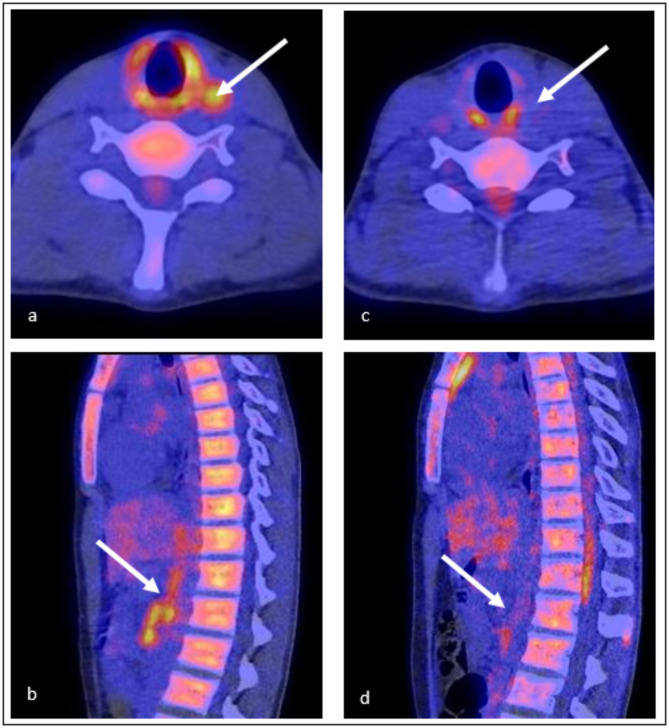

Abstract Image